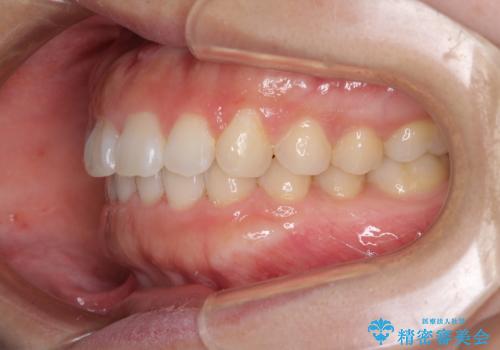

- 前歯のデコボコを治したいとのことで来院された患者様です。

上下顎ともに歯列全体の側方拡大とIPR(歯と歯の間を削る)によってデコボコが解消するように設計し、インビザラインにより治療を行うこととしました。

後方移動に際し、残っていた上顎の親知らずを抜歯することとしました。

1日22時間の装着時間をしっかり守ってくださったので、1年程度で治療を終えることができました。

1セットのマウスピースで概ね治療を終えたのですが、前歯僅かな叢生が残ったため、2セット目のマウスピースで仕上げました。

気にしていた口元の印象が改善され、患者様には大変満足していただきました。